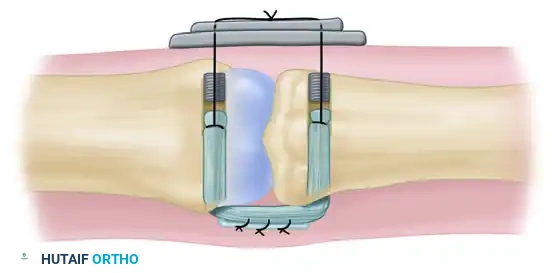

Restoration of coronal alignment achieved by a segmental graft from the palmaris longus tendon attached through transosseous tunnels.

Diagrammatic representation of the reconstruction of the collateral ligament of the proximal interphalangeal joint with a tendon graft. The graft is passed through the transosseous tunnels.